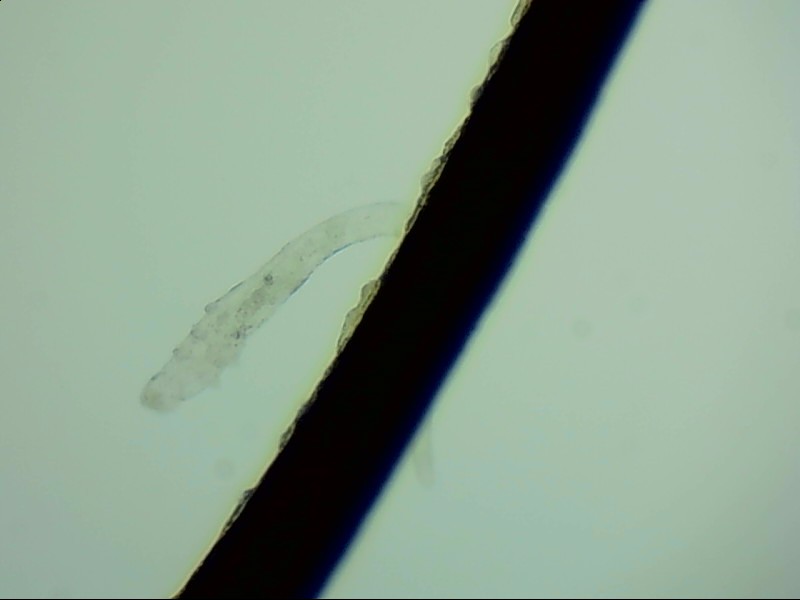

睫毛根部的蠕形螨

蠕形螨是自然界中常見的生物,在人的身上有兩種,分別是毛囊蠕形螨和脂質(zhì)蠕形螨,人身上以毛囊蠕形螨為主,它們主要生活在睫毛根部。

在電子顯微鏡下我們才能看到睫毛根部的一只只蠕形螨,它們不但會(huì)啃食睫毛根部附近的油脂,讓睫毛長(zhǎng)的東倒西歪,還會(huì)給眼睛帶來發(fā)癢、干澀、瞼緣炎充血、在睫毛根部留下袖套狀的分泌物等各種各樣的癥狀,拉低患者的生活質(zhì)量。